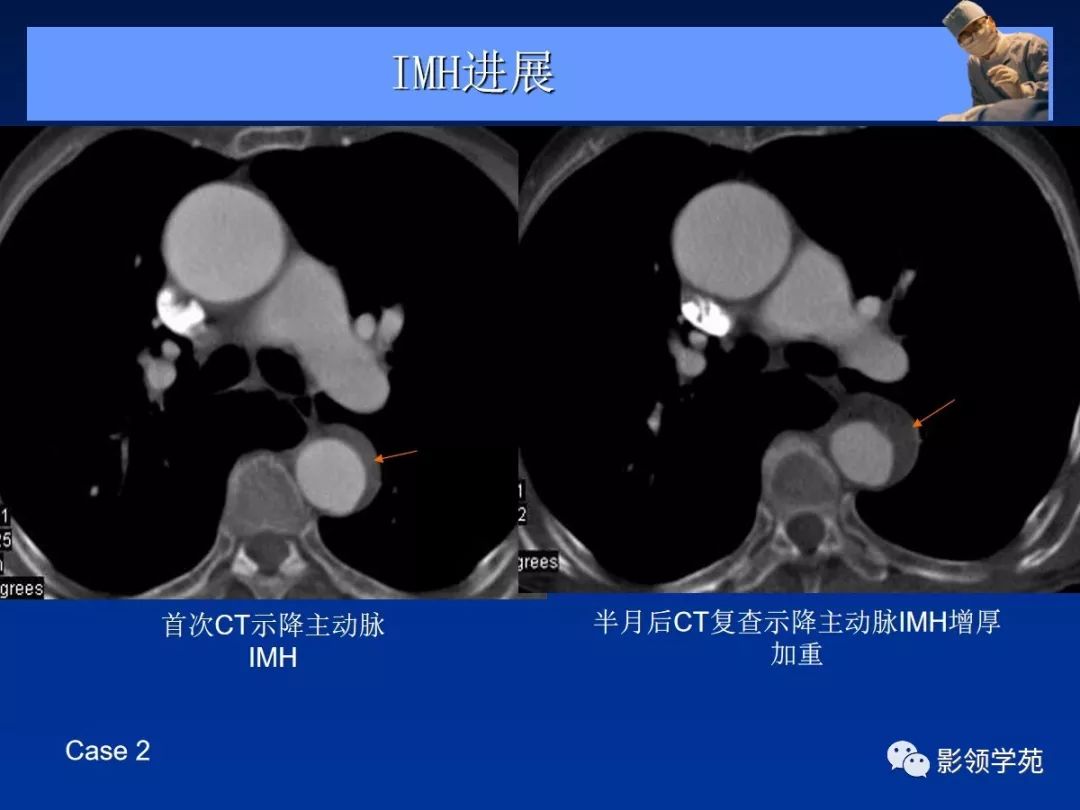

- 主动脉壁内血肿 ( intramural aortic hematoma, IMH)